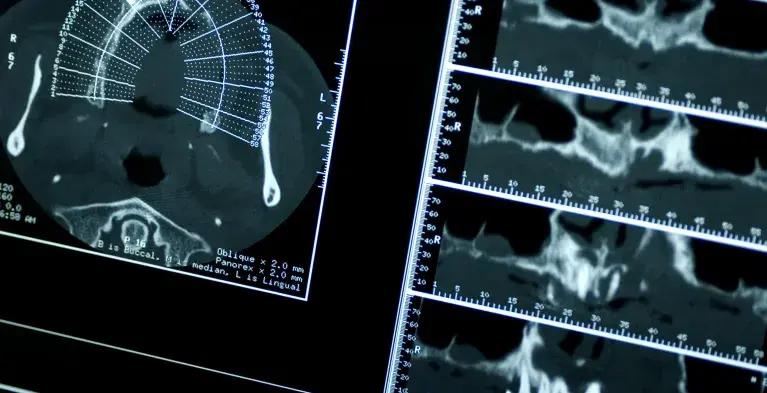

CBCT

Dat je als tandarts extra scholing nodig hebt om Conebeam CT-opnamen te mogen maken en beoordelen is algemeen bekend. Maar dat er ook scholing vereist is voor het verwijzen om deze scans te laten maken, dát weten veel tandartsen niet.

Als je als tandarts je patiënt wilt verwijzen voor het maken van een Conebeam CT-scan, dan heb je volgens de richtlijn Tandheelkundige radiologie kennis nodig over:

• indicatiestelling voor Conebeam CT onderzoek in de tandheelkunde;

• stralingsbelasting van Conebeam CT in relatie met de diagnostische vraagstelling;

• kennis van diagnostiek op Conebeam CT beelden.